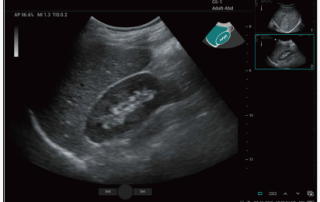

Mindray Ultrasound Consona N9